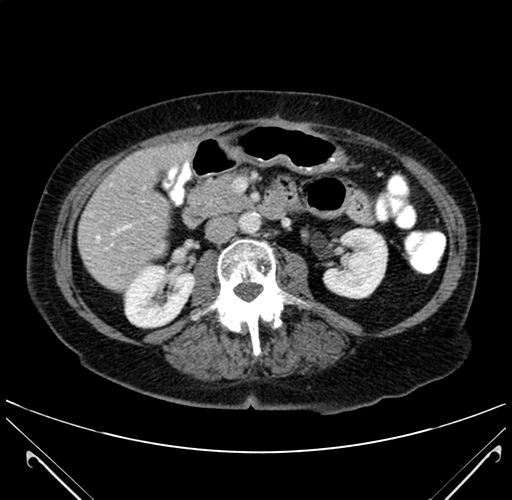

Pre-Chemo: Axial Venous

Axial Venous